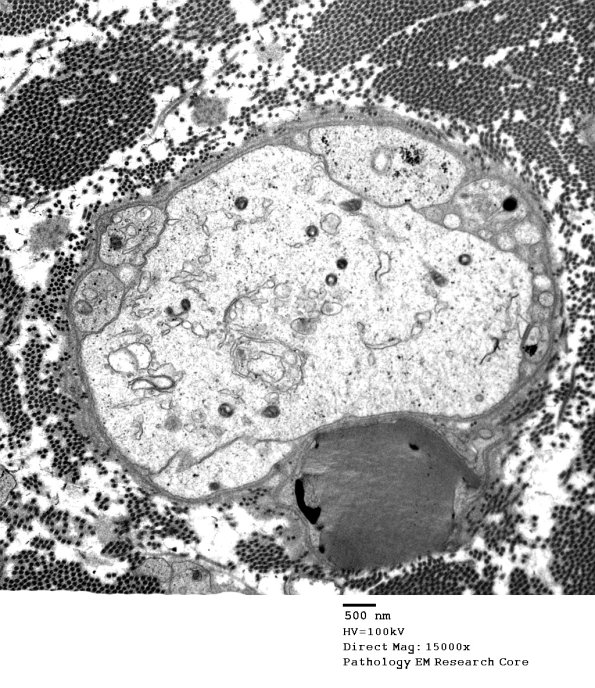

Washington University Experience | PERIPHERAL NEUROPATHY | 0 PNS ARTIFACTS | 3A1 pseudo-demyelinated axons EM 027 - Copy

3A1,2 In this case the large structure is accompanied by small Schwann processes with a similar cytoplasmic appearance and again lacks an axonal cytoskeleton. Occasionally higher magnification examination will show endoplasmic reticulum with ribosomes. (electron micrograph)